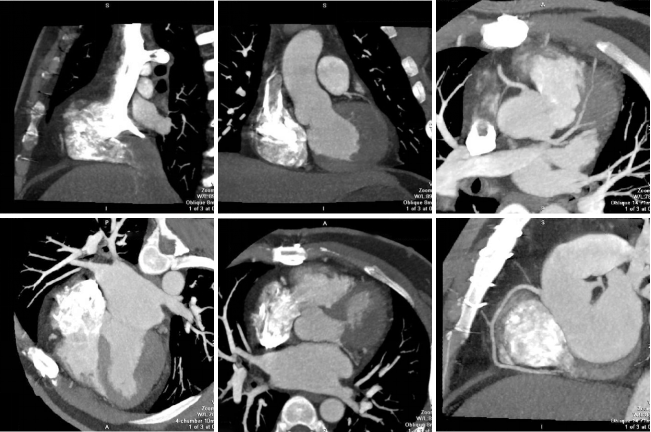

病例二 女,63歲,以持續(xù)性腹部疼痛不適半天就診。既往有冠心病15年、心房纖顫史5年余;高血壓5年。

采用心臟+主動(dòng)脈血管一站式檢查,可見(jiàn)該患者腸系膜上動(dòng)脈及其分支充盈缺損,同時(shí)顯示左心耳內(nèi)多發(fā)血栓, 隨時(shí)有血栓脫落的危險(xiǎn)。

全麻下行剖腹探查、 腸系膜上動(dòng)脈血栓取出術(shù), 病理顯示血栓樣組織機(jī)化。

患者術(shù)后第三天,由于右側(cè)肢體活動(dòng)障礙,語(yǔ)言受限,急查CT發(fā)現(xiàn)多發(fā)腔隙性腦梗塞,MRI檢查后明確左側(cè)急性梗死。

腸系膜上動(dòng)脈栓塞栓子多來(lái)源于心臟,也可來(lái)自于主動(dòng)脈壁粥樣硬化斑塊脫落。腸系膜上動(dòng)脈從腹主動(dòng)脈分出,主干口徑又較大,脫落的栓子易于進(jìn)入,在血管狹窄或分叉處導(dǎo)致血管栓塞。

臨床表現(xiàn)主要有“Bergan三聯(lián)征”1 、劇烈而沒(méi)有相應(yīng)體征的腹痛。2器質(zhì)性心臟病和并發(fā)心房纖顫的心臟病。3、胃腸排空障礙表現(xiàn)如腹瀉、 血便。

640層寬體探測(cè)器CT掃描速度快,可進(jìn)行大范圍心血管一站式檢查,快速排除血管病變,且由于探測(cè)機(jī)單元只有0.5mm,對(duì)于一些微小的病變也能清晰顯示。